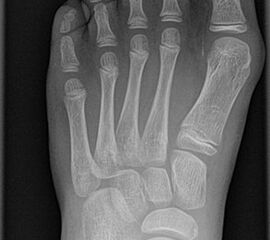

Davon abzugrenzen ist der Hallux valgus interphalangeus ohne zugrundeliegenden Spreizfuß. Hierbei handelt es sich um eine Fehlstellung des Grundgliedes bei dem der mediale Anteil länger ist als der laterale und dadurch die distale Gelenkfläche des Grundgliedes am Endgelenk valgisch steht. Das Grundgelenk steht orthograd. Möglich ist darüber hinaus eine Kombination aus einer Hallux valgus Fehlstellung mit Hallux valgus interphalangeus Deformität.

Beim Hallux valgus interphalangeus sind Jungen 3x häufiger betroffen als Mädchen (Lamprecht 2015).

Beim Hallux valgus interphalangeus treten lateral bei Druck gegen die zweite Zehe Beschwerden auf, bis hin zu Nagelentzündungen im Sinne eines Unguis incarnatus. Häufig kommt es zu einer Flexionsstellung im Endglied das dann Schuhdruckprobleme und auch Schmerzen sowie Beschwielung medial am Interphalangealgelenk über der medialen Kondyle des Grundgliedköpfchens hervorruft.

• Hallux valgus interphalangeus Winkel